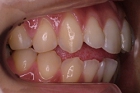

CASE1

前歯の歯並びが悪いのが一番気になります。

右側では良く噛めません↓(16歳/女性)

||||||||

概要・担当医コメント:叢生・右側咀嚼障害↑

マルチブラケット装置/動的治療期間26ヶ月(23回)

/費用概算:60万円

高校の部活も矯正も両方頑張れたそうです。

上顎右側の小臼歯を1本のみ抜歯させていただき,あとは上下の歯列アーチ形態の修正にて矯正できました。